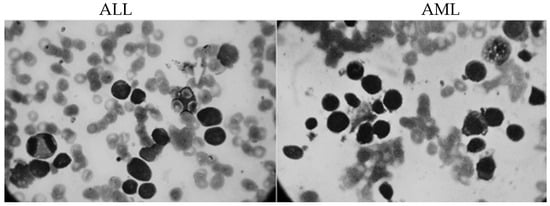

3.1. Data Collection